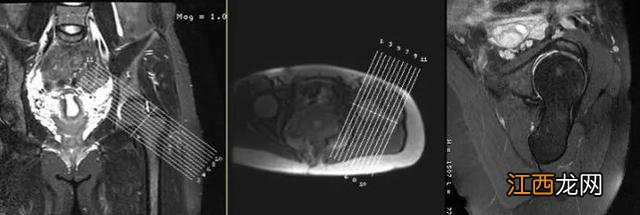

在标准横轴面上定位线垂直于股骨颈,标准冠状面上定位线平行于股骨颈可以得到斜矢状面图像 。

相位编码方向为前后方向 。

采用过采集技术,右侧髋骨图片,防止卷折伪影 。

采用较短TE值,短回波链的高分辨率扫描更有利于显示髋骨关节软骨、盂唇结构 。

斜矢状面主要用于观察前盂唇及后盂唇,即8点至11点方向和3点至5点方向 。